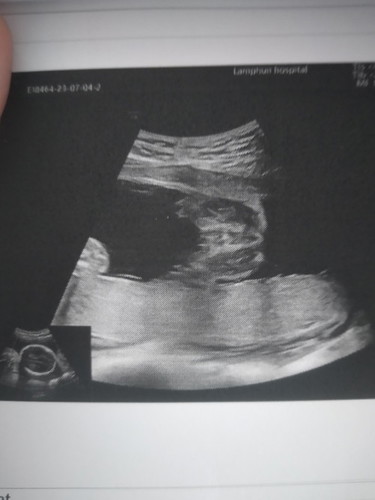

อันนี้คือเพศใช่ไหมคะ

อยากรู้ว่าใช่เพศไหมถ้าใช่นี้คือได้เพศอะไรคะ

ลูกสาวคะแม่เป็นกลีบเลย

ผู้หญิงค่ะแม่

ลูกสาวจ้า